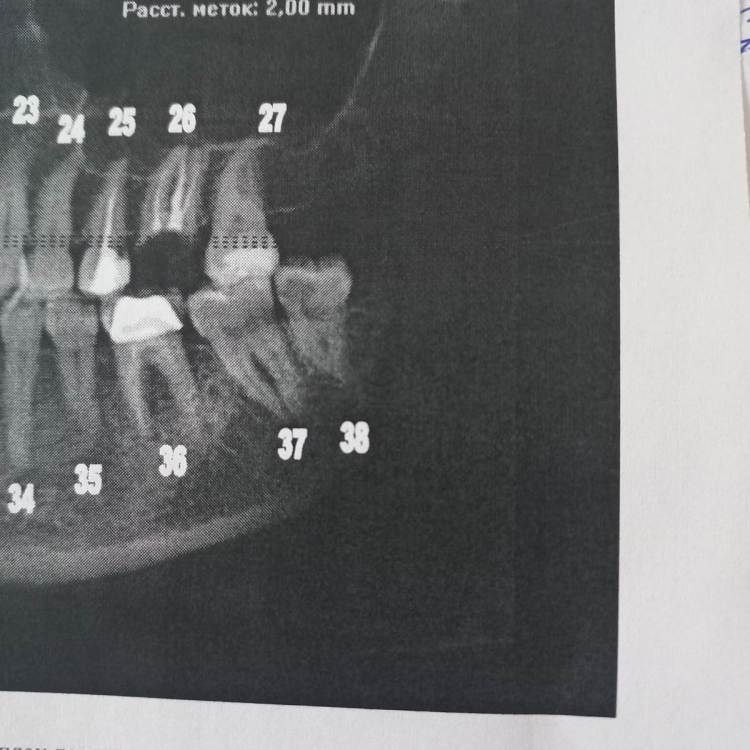

Еленаkjj Опубликовано 18 декабря, 2022 Поделиться Опубликовано 18 декабря, 2022 Здравствуйте! Нужно удалить 38-ой зуб и возможно 48 (один доктор сказал, что можно вылечить). Решение вопроса осложняется непереносимостью анестезии с адреналином и общим состоянием здоровья (заболевание печени, синдром активации тучных клеток). Общий наркоз и седация (большая лекарственная нагрузка) тоже противопоказана в связи с общим состоянием здоровья. Анестезия без адреналина (ультракаин Д, скандонест) действует, но слабо и недолго. Недавно удаляла корни разрушенного 26-го зуба под ультракаином Д. Длилось это минут 40. Корни распиливали и удаляли по одному. Было больно. На последнем корне было настолько больно, что колотящееся сердце остановилось, потемнело в глазах, до обморока не дошло, но было близко к тому. Я резко села на кресле, стала часто дышать и немного отпустило. Потом еще час было общее плохое состояние. 38-ой зуб сильно разрушен внутри. Там разрушение идет почти по всему периметру зуба, между коронкой и десной образовалась кариозная полоса. Зуб живой. С учетом непереносимости адреналина и недавнего болезненного опыта удаления 26-го с анестезией без адреналина стоит ли попробовать удалить 38-ой зуб с помощью ультразвука? Поможет ли такой метод минимизировать в моем случае боль и какие противопоказания у ультразвука? Ссылка на комментарий